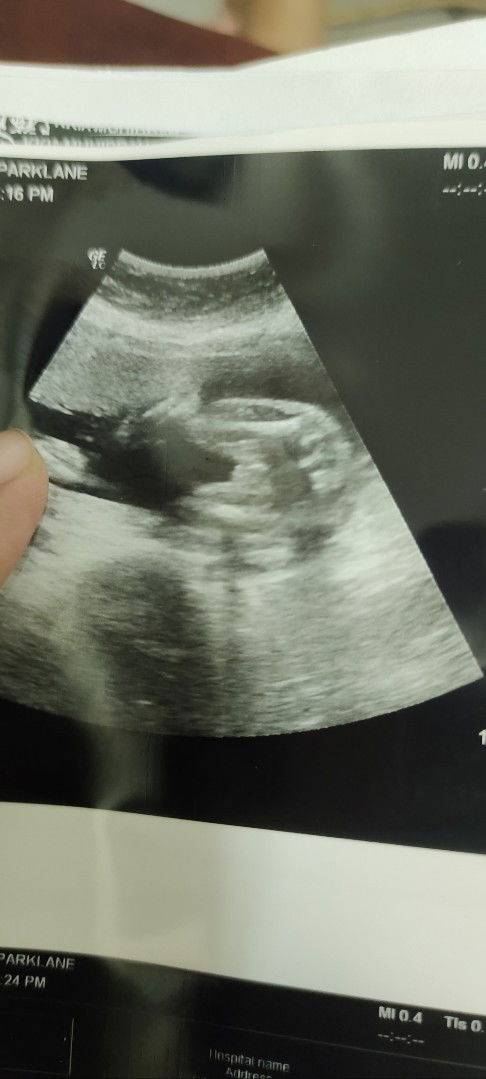

Hi gais. I ni FTM. Minggu ni I pregnant hampir nak 30 weeks. Pagi td pegi hospital minum air gula. Sebelum minum air gula memang dah sangkut, nurse bagitau dalam 7. Lepas minum air gula pulak dalam 14. Risau pulak ni. Tapi malam ni I cuba check sendiri lepas makan malam dalam 2 jam dapat bacaan 6.2 pulak. Ada orang lain tak sama macam ni?? Boleh share experience tak? Susah hati sebab kalau gdm sangkut kena makan metformin dan inject insulin. Belum lagi part kena surrender awal untuk induced labour n ceaser. #Needadvice #firstmom